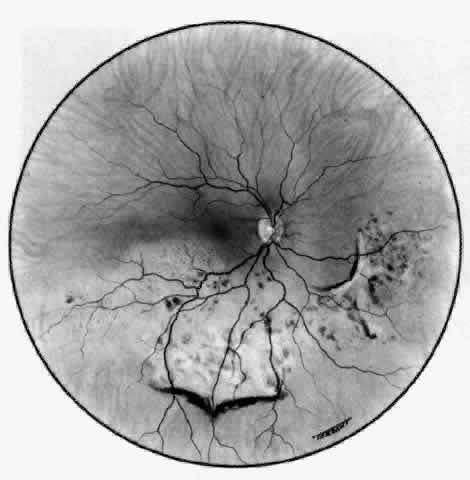

Posterior Scleritis

Because the posterior sclera is invisible, the diagnosis of posterior scleritis is made only if the anterior sclera is also involved or some other sign or symptom leads one to suspect it. Posterior scleritis is much more common than previously suspected, as recent clinical and pathologic studies have shown.19,28,29 There are two distinct forms of posterior scleritis. The first is usually associated with an anterior scleritis. This granulomatous disorder, like its anterior counterpart, can be diffuse, nodular, or necrotizing in character and is associated with the connective tissue diseases. The second form occurs in young patients of all races who are 9 to 40 years of age. It is always diffuse in character but is not associated with any systemic disorder. Both forms may cause uveitis if the inflammation affects the ciliary body, and in both forms the patient may develop exudative retinal detachments, choroidal folds, and swelling of the disc (Figs. 51 and 52). The granulomatous type may also involve the structures outside the globe, causing proptosis (Fig. 53), limitation of ocular muscle movement, and, uniquely, retraction of the lower lid on attempted elevation of the eye (Fig. 54). Diagnosis is with B-scan ultrasonography.

Fig. 52. Fundus appearance after resolution of exudative detachment in patient with severe posterior scleritis. Macula was affected and vision much impaired. (Watson PG: Management of scleritis. In: Recent Advances in Ophthalmology, Vol 5. London, Churchill-Livingstone, 1975)